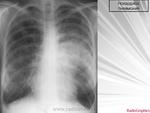

Двусторонняя интерстициальная. Гипертрофия правого корня, перисциссурит малой щели справа. Как бы не вылез центральный справа с лимфогенными метастазами.

Раковый лимфангит скорее всего

возможен чаще всего у человека пожилого возраста. Возраст пациента не указан. Сходную картину может дать саркоидоз органов дыхания II. Диагноз за клиницистами с учетом всех результатов обследования. При интерстициальных заболеваниях легких показазано КТ-исследование, если имеется такая возможность.

Выскажусь, как и в параллельной ветке, за диссеминированный туберкулез. Наверное, здесь можно предположить казеозный очаг (л/у?).

Первая мысль о раке.Но не спешим,назначим контроль,как при пневмонии.

доктора Дмитрия Волегова. Диссеминированному туберкулезу лимфогенного генеза не противоречит преимущественная локализация очагов в средних и нижних отделах легких, особенно у больных с наличием Вич-инфекции.

Не поддержу версию туберкулёза.У ВИЧ-инфецированных она симметрична,как правило.

Если КТ под рукой есть, то лучше не тянуть время.. Изменения явно интерстициальные, на простую пневмонию никак не тянут. Было несколько пациентов с раковым лимфангитом - выглядело это все именно так как на этой ФЛГ

+1. Пнемония как уже сказано, интерстициальная. В дифференциально-диагностический ряд можно выставить и раковый лимфангаит, оздачить клиницистов, но как-то в этом плане не очень убедительно.

Возраст пациента весьма пожилой, в районе 60 лет.

Температура у пациента в течение двух недель в районе 37 с небольшим, только сегодня назначены антибиотики.

Наличие интерстициальных и узелковых изменений легких, в сочетании с патологией плевры, предполагает наличие лимфангического карциноматоза.

В пользу лимфангита еще преимущественное распространение в средних и нижних отделах, неструктурные корни, еще cuffing (разбухание?) стенки бронхов, подчеркнутость междолевых щелей (на боковом хорошо видно, средняя доля "выделена")